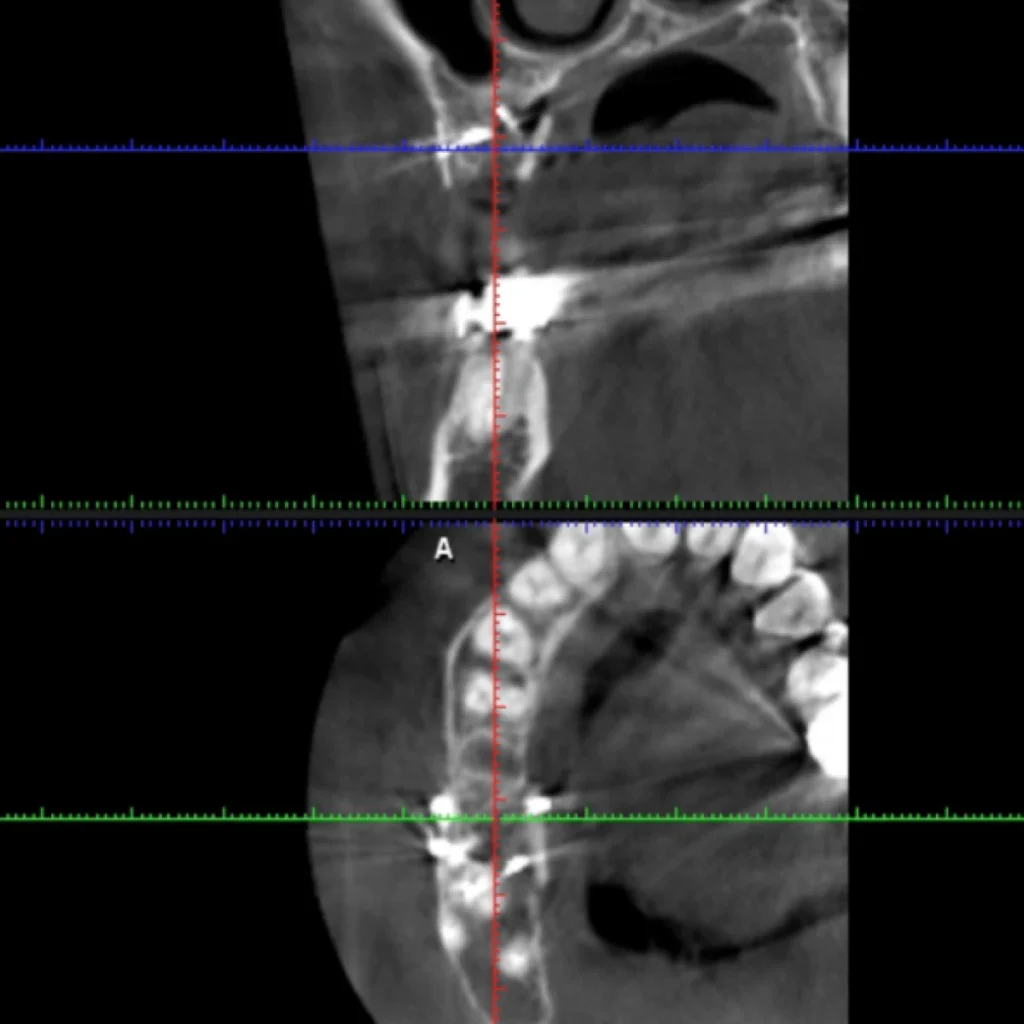

Un cone beam (équivalent d’un scanner) est réalisé sur place afin de valider le diagnostique et de vous proposer le traitement adapté à votre situation. Certaines font intervenir des biomatériaux (os de banque d’origine humaine ou animale; os de synthèse; os autogène prélevé directement dans votre bouche lors de l’intervention).

- Le scanner réalisé au cabinet met en évidence un défaut osseux majeur nécessitant une greffe osseuse complexe pour réhabiliter la zone par 2 implants.

- Après 4 à 6 mois de cicatrisation, un scanner est à nouveau effectué pour s’assurer du bon volume osseux pour mettre en place nos implants.